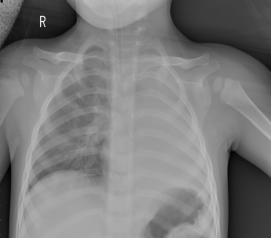

2017年7月29日晚,一辆救护车的鸣笛打破了四川省妇幼保健院夜晚的宁静。车上一名一岁多的小女孩由外院转运,经医院急诊科绿色通道快速进入重症医学科抢救。当时孩子气促、口唇发绀,左侧肺部呼吸音消失,生命垂危。时间就是标尺,重症医学科医护团队快速反应,立即给予孩子气管插管、呼吸机辅助通气治疗,在维持孩子的氧合前提下,放射科顺利完成了床旁胸片检查,而胸片的结果却让在场所有医务人员捏了一把汗:孩子的左肺竟然“不见了”?!

随后,重症医学科会同儿外科、儿科、耳鼻喉科、麻醉科等多学科专家一起讨论孩子的病情,基本排除肺发育异常和肿瘤的可能性,方向最终锁定支气管内异物或是塑型性支气管炎。若是塑型性支气管炎,除了用纤维支气管镜取出堵住气道的塑型物外,别无他法。若是支气管内异物,孩子目前在有创通气支持下氧合仍不稳定,无法承受在全麻术下支气管硬镜行异物取出术的风险。此时医疗团队面对的最大困惑就是在形形色色的不确定性中如何最大限度降低风险,挽救孩子的生命。面对孩子父母的信任和期待,谢成副主任充分与家属沟通后,毅然决定承担风险压力,充分做好各种突发情况的应急准备后,在ICU里进行床旁纤维支气管镜取异物术。手术中,医护团队密切协作,一边严密观察孩子生命体征,保证有效氧合,一边由谢主任小心翼翼钳取堵塞物,将堵塞的东西一点点取出后,才发现造成孩子生命危险的罪魁祸首,原来就是小小的半粒花生米和围绕着花生米周围异常粘稠的痰栓。当左主支气管的堵塞物全部清除后,气道内又涌出大量的脓痰,继续利用纤维支气管镜给予气道灌洗治疗,清除脓痰后孩子左肺的通气得到改善。整个手术持续近2个小时,手术结束时大家的工作服已经被汗水湿透。术后1小时复查胸片,孩子的左肺又“回来”了!